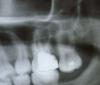

Bier Опубликовано 31 июля, 2009 Поделиться Опубликовано 31 июля, 2009 1. каналы запломбированы не ахти.2. Имеется нависающий край пломбы дистально и патологический карман там.3. Отсутствует нормальный контактный пункт с 7м зубом из-за плохой пломбы (а) и выдвигающегося вниз 7го зуба (б). 7й зуб выдвигается вниз т.к. внизу нет антагониста. З.Ы. если что - то удаление вашего зуба не проблема. И скорее всего никакая пазуха не вскроется. Но мне кажется, если вопросы все с этим зубом решить, боли уйдут. Ссылка на комментарий

Bier Опубликовано 1 августа, 2009 Поделиться Опубликовано 1 августа, 2009 это последние снимки? или после них что-то делали?Судя по всему боли из-за кармана между 26 и 27 зубами. Эх, найти бы силы опять пройти все это.За 6 лет уже разочаровалась, столько сделано, а толку ноль.ну вы с какой целью задали вопрос? что мы по интернету решим вашу проблему? Нет, мы можем только дать направление вашим дальнейшим действиям. На форуме много хороших врачей, обратитесь к тому, кто вам больше нравится. Ссылка на комментарий

АНРОША Опубликовано 1 августа, 2009 Поделиться Опубликовано 1 августа, 2009 каналы в 6 зубе перелечивать, потом протезировать (вкладка+коронка), найти пародонтолога, который сможет разобраться с карманом Ссылка на комментарий

Scrabble Опубликовано 5 августа, 2009 Поделиться Опубликовано 5 августа, 2009 6-ой перелечить однозначно-у эндодонтиста. Пульпит в 7-ом тоже возможен. Ссылка на комментарий

олег1965 Опубликовано 6 августа, 2009 Поделиться Опубликовано 6 августа, 2009 6-ой перелечить однозначно-у эндодонтиста. Пульпит в 7-ом тоже возможен. + поискать второй щёчно-медиальный канал Ссылка на комментарий